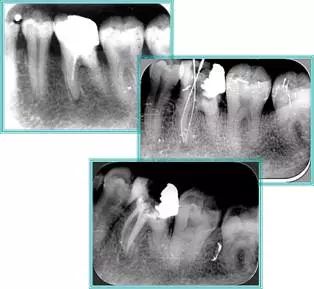

6. 术后 X 线片

术后 X 线片用来评定根管充填 长度、致密度(管壁清晰、侧枝)等指标。

牙胶尖什么颜色​牙齿“晓”“技”|最全根管治疗的标准步骤,以及细节把握_https://www.jmylbn.com_新闻资讯_第16张

左图为根管充填术后 X 线片。图中可见,根管充填较好。右下图有白色小点,为侧方加压导致糊剂挤出所致,表明根管充填比较致密。

致密、恰到好处的充填可去除干净根管里感染灶,机体逐渐恢复。

牙胶尖什么颜色​牙齿“晓”“技”|最全根管治疗的标准步骤,以及细节把握_https://www.jmylbn.com_新闻资讯_第17张

多根牙时候需进行偏移投照,正位投照无法说明具体哪根牙根管充填效果。        二、根管预备及充填要求